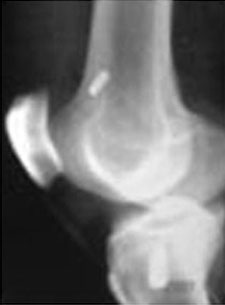

Post-op X-ray